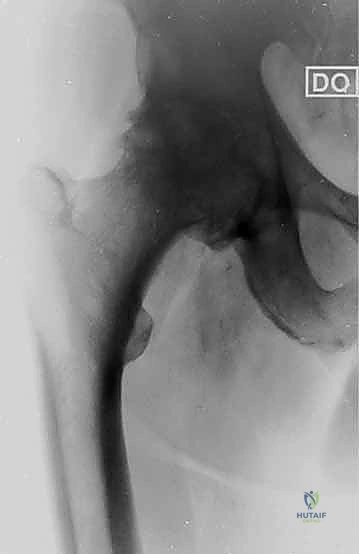

2. التصوير الشعاعي (X-Rays)

تُعد الأشعة السينية القياسية الأداة الأهم في تشخيص خشونة الورك. يبحث الدكتور هطيف عن أربع علامات كلاسيكية في الأشعة:

* تضيق المسافة المفصلية (Joint space narrowing) نتيجة فقدان الغضروف.

* تكوّن نتوءات عظمية (Osteophytes).

* تصلب العظم تحت الغضروفي (Subchondral sclerosis) حيث يظهر العظم أبيض وكثيفاً نتيجة الاحتكاك.

* تكيسات عظمية (Subchondral cysts).